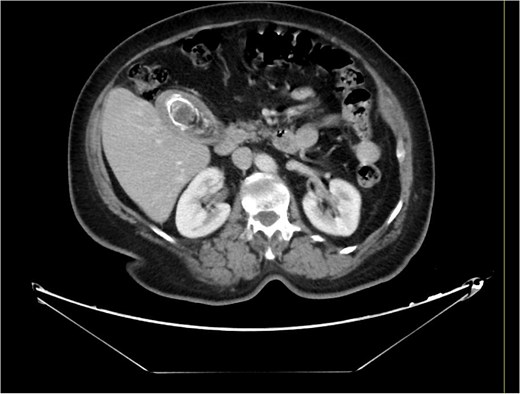

A 63-year-old obese female, known to have hypertension and diabetes, was admitted electively for laparoscopic cholecystectomy and laparoscopic incisional hernia repair with mesh. Prior to surgery, the enhanced computed tomography scan revealed a fat- containing supraumbilical hernia measuring 1.5 cm, a 54 mm gallbladder stone, and unremarkable liver pancreas, spleen, kidneys, and pelvis organs, with no evidence of intra-abdominal free air or fluid (Figs 1 and 2). The patient underwent surgery under general anesthetic using standard sterile procedures. We began with a supraumbilical incision ⁓3 cm above the umbilicus over the previous hernial site. After making a 1 cm longitudinal incision, we identified and opened the fascia, introducing a 12 mm port without immediate complications. The camera was inserted, gas was insufflated, and the abdomen was explored, revealing no immediate injury. An additional 11 mm port was inserted in the left upper quadrant for further exploration. Severe adhesions of the small bowel to the abdominal wall were noted. The first port was examined, and no bowel injury was found. LigaSure was utilized for adhesiolysis, followed by the insertion of two 5 mm ports in the right upper and lower quadrants, and a 5 mm port in the epigastric area. Laparoscopic adhesiolysis was performed, releasing the adhesions without bowel injury. The gallbladder, severely adhered to the liver bed, was identified, retracted cephalad, and Calot’s triangle was achieved. The cystic duct was identified, double clipped, and divided, followed by dissection, clipping, and division of the cystic artery. Intraoperatively, we consulted a senior consultant to confirm the anatomy. The critical view of safety was achieved, and the gallbladder was dissected from its bed. Spillage of gallbladder contents occurred, which was suctioned and controlled. The gallbladder was retrieved through the supraumbilical port using an Endobag without complications (Figs 3 and 4). Hemostasis was secured after examining the liver bed, followed by multiple irrigations and suctioning. The hernial defect was examined and found to be a small incisional hernia (⁓1 × 0.2 cm) containing only fat. After releasing the adhesions, a mesh was applied, tailored to the defect size, and secured with endo-tuckers. Hemostasis was ensured, and a JP drain was inserted under vision and secured with Prolene. All parts were removed under vision, and the skin was closed using clips. The patient tolerated the procedure well and was transferred to the Post Anesthesia Care Unit in stable condition.

Computed tomography of the abdomen and pelvis before the procedure.